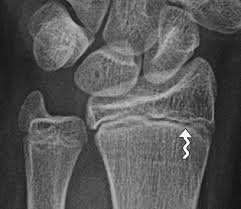

Think of the epiphyseal line as a permanent mark that tells us the bone has finished growing. You can see this line on an X-ray, and it’s helpful for doctors to determine bone age, which is particularly important for evaluating growth and development in children and adolescents.

For example, if a doctor sees that a child’s epiphyseal lines are still open, it means that the child is still growing. Conversely, if the epiphyseal lines are closed, it means that the child has reached their full height. This is also useful for understanding the healing process after a bone fracture. The presence of an epiphyseal line can help determine the location of the fracture and the extent of bone growth that has occurred since the injury.

The presence of an epiphyseal line on an x-ray indicates that the bone has finished growing in length.

When epiphyseal closure is complete, a line appears on the x-ray where the epiphyseal plate used to be. This line is called the epiphyseal line.

Epiphyseal lines are a good indicator that a person has reached their full height. They can also be useful for determining a person’s age, especially in children.

Here’s the thing: we can’t actually see the growth plates directly. They’re inside the bone. But, we can use X-rays to see the epiphyseal line, which is like a ghost of the growth plate once it’s closed.

The epiphyseal line will show up as a thin, dense line on the X-ray. It’s not super obvious, but an experienced doctor or radiologist can spot it.